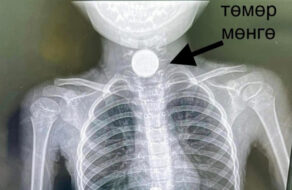

ЭХЭМҮТ-ийн Ерөнхий мэс заслын тасагт гадны биет залгисан бага насны хүүхэд иржээ. Рентген зураг авахуулахад хүүхэд зоос залгисан байсан бөгөөд улаан хоолойн нэгдүгээр нарийсалд буюу хамгийн дээрээ байсан учир...